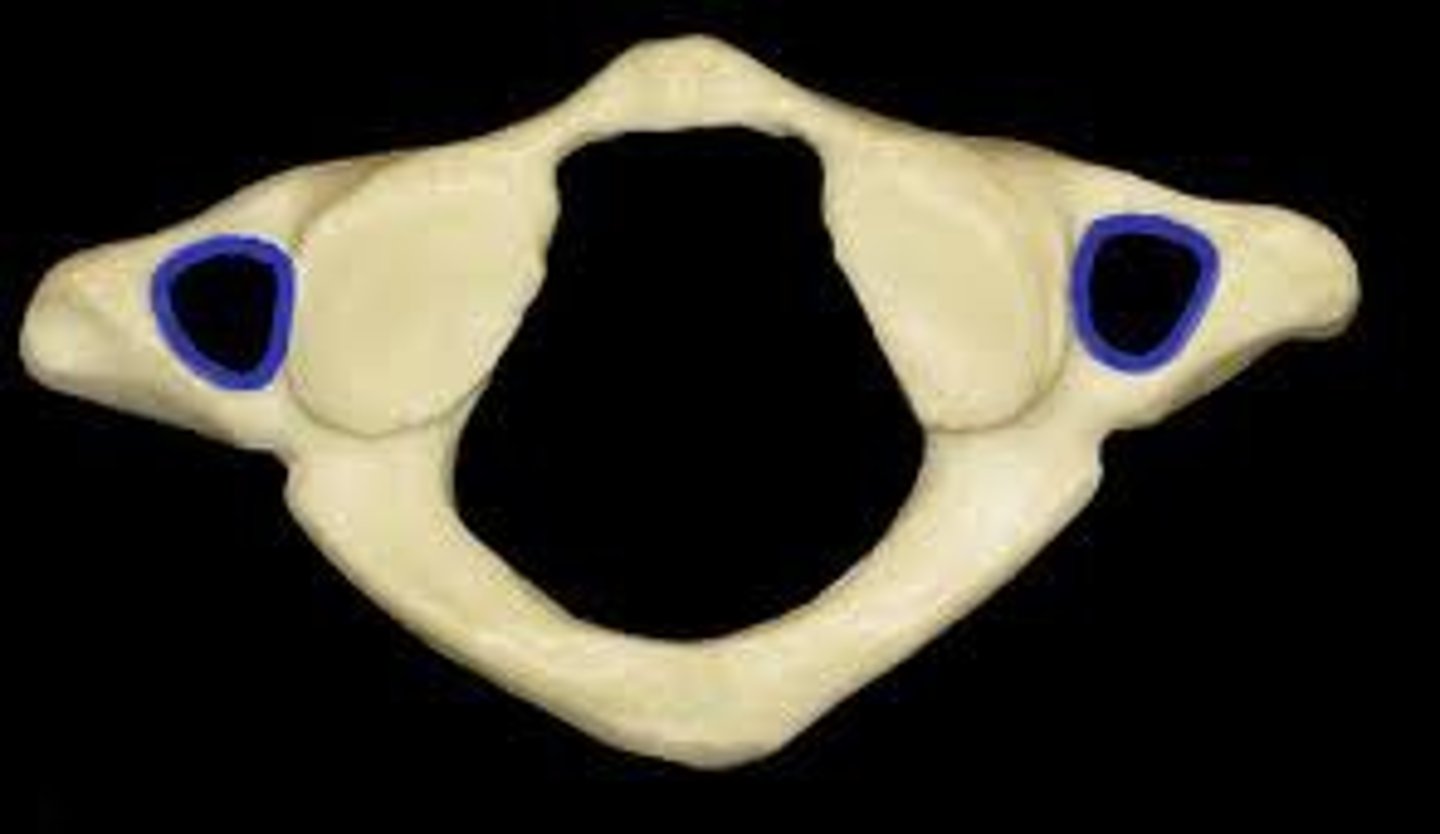

atlas C1

what vertebra is considered the atlas

hold head up

what is the purpose of C1

what vertebra is visually a flat bone